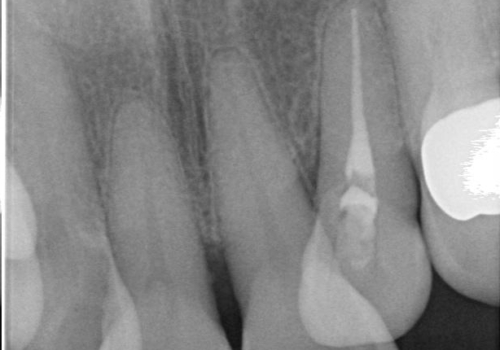

- 下の前歯(左下2)と奥歯の動揺がひどくなってきたことを主訴に来院された患者様です。

精査したところ、前歯の咬み合わせが反対になっていること、下の奥歯(下顎両側67)が4本欠損していることから動揺が生じていました。

入れ歯も抵抗があるとのことから、相談を重ね、今の状態では保存不可能な下の前歯(左下2)を抜去し、ブリッジや連結補綴により動揺を抑えることにしました。

また、咬み合わせが反対になっている上の前歯(左上2)も補綴で形を変えることにより、咬合を改善しました。

下顎大臼歯が欠損したままで今ある歯に負担がかかりやすいことから、長期的予後は保証できないことをご理解頂いた上で治療を行いました。